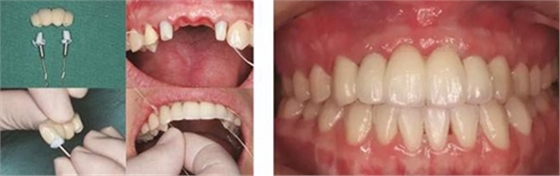

圖35 預(yù)粘接 圖36 戴入全瓷修復(fù)體正面觀

圖37 戴入全瓷修復(fù)體局部舌側(cè)觀 圖38 永久修復(fù)后微笑

圖39 永久修復(fù)后大笑

③患者試戴個(gè)性化氧化鋯基臺(tái),檢查基臺(tái)就位情況,咬合狀況,基臺(tái)邊緣位于齦緣下<1mm,試戴氧化鋯基底,確認(rèn)基底就位良好,邊緣密合,完成永久修復(fù)體的制作。口內(nèi)戴入氧化鋯基臺(tái)后,扭矩扳手加力至30N后,聚四氟乙烯封閉螺絲通道,樹脂封孔。試戴全瓷修復(fù)橋體,檢查冠邊緣與基臺(tái)邊緣緊密接觸,與周圍軟硬組織相協(xié)調(diào),確認(rèn)鄰接以及修復(fù)體顏色良好。調(diào)整咬合,靜態(tài)咬合:正中咬合時(shí)后牙區(qū)均勻接觸,輕咬合時(shí)前牙區(qū)無(wú)接觸,重咬合時(shí)輕接觸,無(wú)牙合干擾或早接觸;動(dòng)態(tài)咬合:側(cè)方運(yùn)動(dòng)時(shí)尖牙引導(dǎo)或前牙組牙功能的交錯(cuò)保護(hù)牙合,前伸運(yùn)動(dòng)是切牙引導(dǎo)牙合,工作側(cè)和非工作側(cè)無(wú)牙合干擾。咬合調(diào)整完畢后高度拋光,口外用硅橡膠制備預(yù)粘接代型,超聲振蕩修復(fù)體,消毒后使用自粘接樹脂水門汀于口外預(yù)粘接并戴入口內(nèi),使用牙線去除多余粘接劑。拍攝X線片,確認(rèn)基臺(tái)和牙冠完全就位。

3、通過制作個(gè)性化轉(zhuǎn)移桿,將種植體周圍軟組織的形態(tài)輪廓精確地復(fù)制并轉(zhuǎn)移到模型上,個(gè)性化制作的氧化鋯基臺(tái)及全瓷修復(fù)體,生物相容性及美學(xué)效果良好,患者對(duì)最終修復(fù)效果滿意。